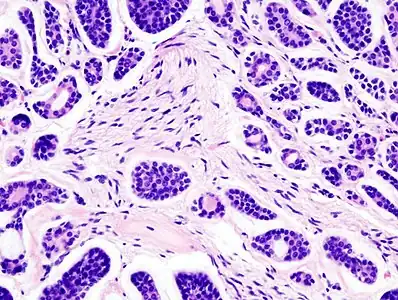

Histopathological image of adenoid cystic carcinoma of the salivary gland infiltrating a nerve (center), H&E stain

Histopathological image of adenoid cystic carcinoma of the salivary gland, immunostain for S-100 protein